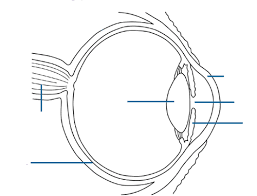

State the main feature on the diagram of the eye. The main features are the cornea, iris, pupil, lens, retina and ciliary muscle.

State the parts of the eye involved with focusing the light onto the retina. The cornea and the lens are involved in focusing the light onto the retina.

Explain the symptoms and cause of short sight. Someone with short-sightedness cannot focus properly on distant objects. This is caused by the eyeball being elongated, so that the distance between the lens and the retina is too great.

Explain the symptoms and cause of short sight. Someone with long-sightedness cannot focus properly on near objects. This is because the lens focuses the sharpest image behind the retina. This defect is often age-related, and due to the lens becoming more crystalline.

Describe how short sight can be corrected. It can be corrected by placing a concave lens in front of the eye.

Describe how long sight can be corrected. It can be corrected by placing a convex lens in front of the eye.